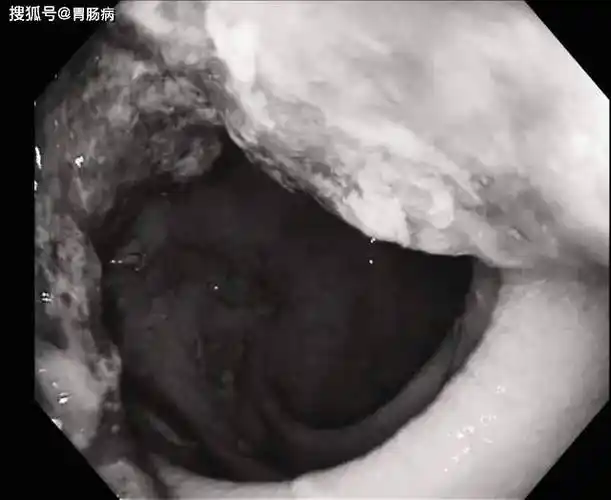

稀便沥青样粘稠有水

今年44岁的常先生是因为最近半年,持续腹痛,大便不成型,伴粘液便,偶尔

黑色焦油状粪便可能是溃疡病引起的内出血,必须尽快止血并排除癌症的